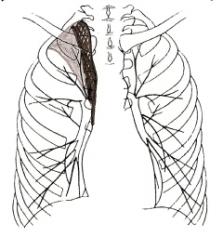

4 фаза развития рака. Просвет бронха обтурирован полностью – иллюстрация 8.

3 степень сужения (полная) бронха – ателектаз характеризуется типичной картиной:

- тень ателектазированной структурной части лёгкого приближается к треугольной форме – иллюстрации 9, 10;

- уменьшение объёма структурной единицы лёгкого;

- смещение и деформация междолевых щелей;

- смещение сосудистых стволов.

Ниже приведены схемы спадения долей и сегментов (по Anacker H., 1963) – иллюстрации 11, 12, 13.